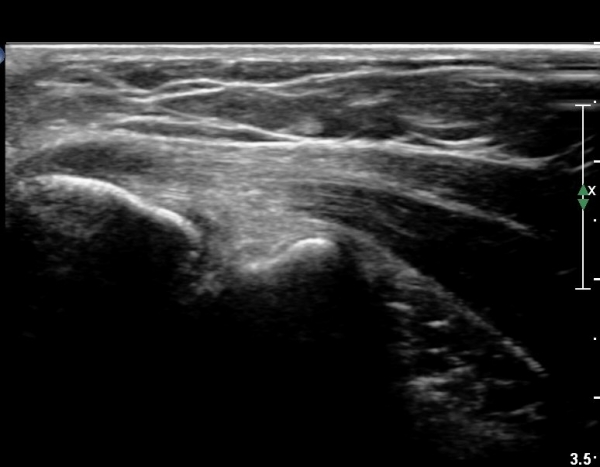

ÃÊÀ½ÆÄ °Ë»ç

³»»ó°ú Á¾´Ü¸é°Ë»ç¿¡¼­ ³»»ó°ú ±¼°ñ°Ç ºÎÂøºÎ¿¡ Àú¿¡ÄÚ º´º¯ÀÌ °üÂûµÈ´Ù. °Ç ½ÉºÎÀÇ

³»ÃøºÎÀδë´Â ƯÀÌ ¼Ò°ßÀ» º¸ÀÌÁö ¾Ê´Â´Ù(±×¸² 1, 2).